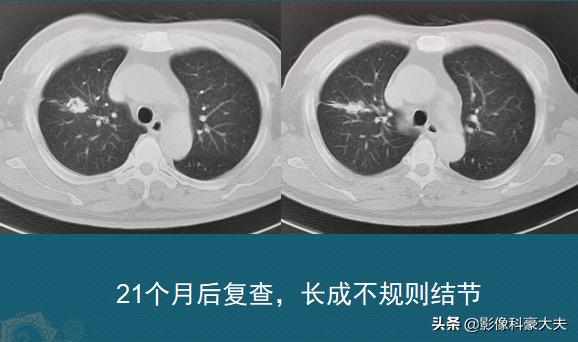

可惜,老人第二次回来的时候,已经是两年后了:

“纤维灶”长成了一个不规则结节状,表面分叶,符合肺癌的表现了。